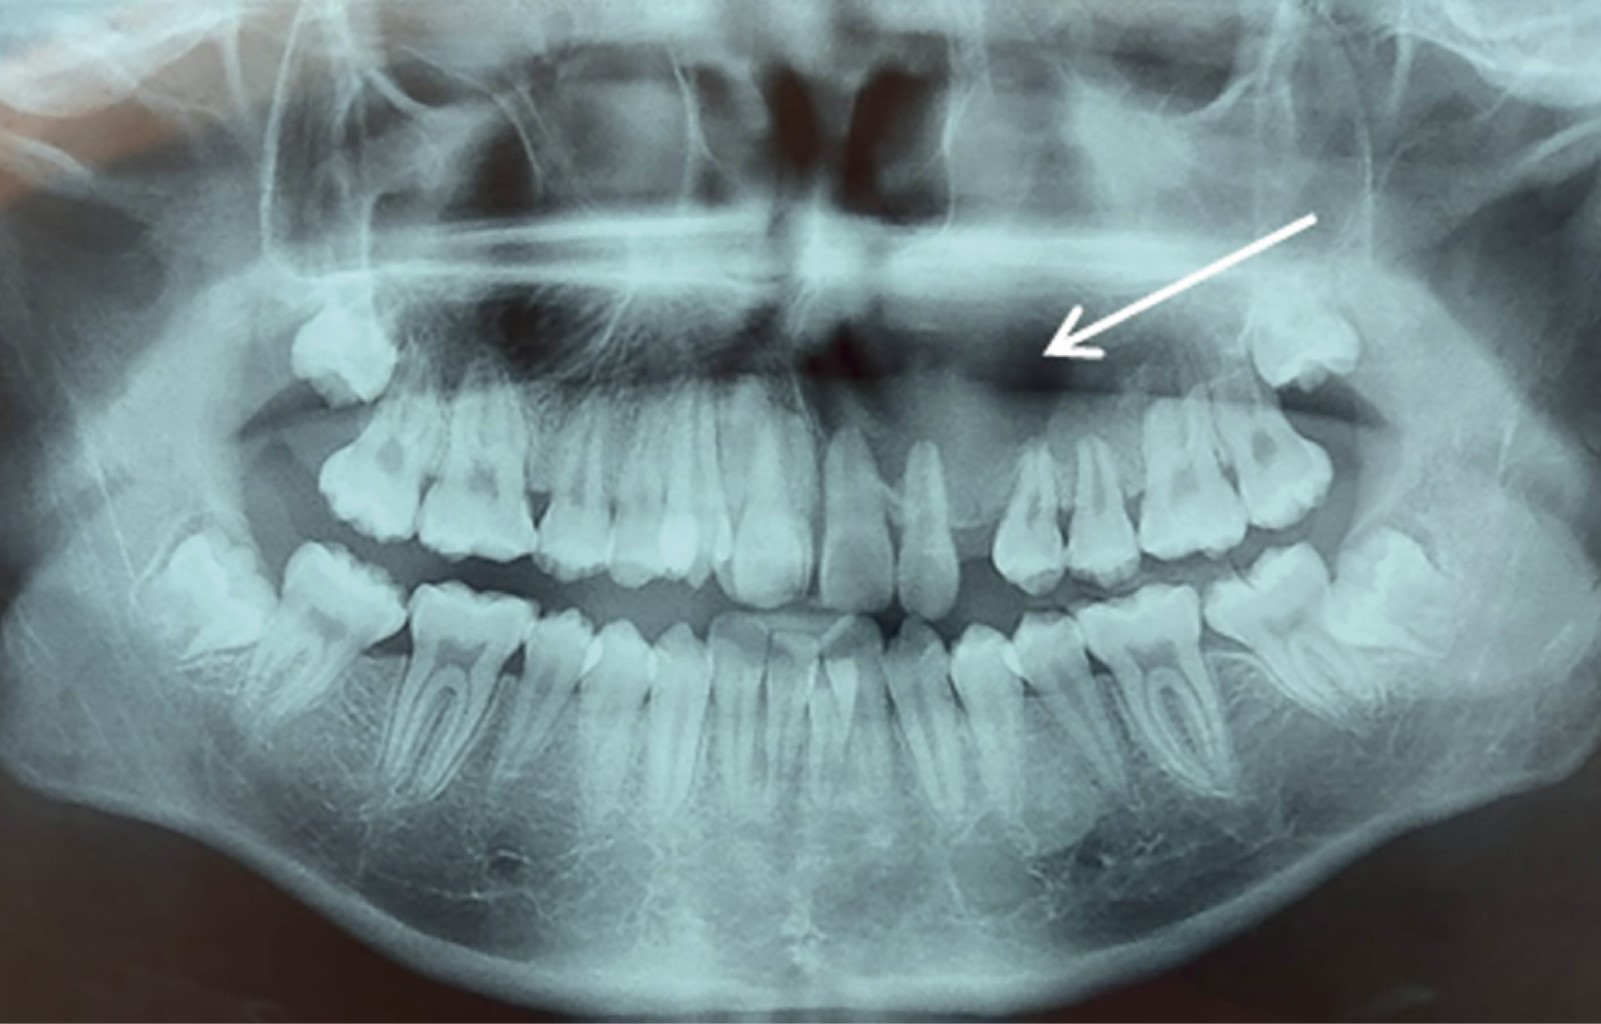

The calcifying odontogenic cyst is defined as a cystic lesion of benign origin originating from epithelial remains during odontogenesis, it presents as an asymptomatic and slow growthing lesion, which affects the anterior region of the mandible and the maxilla, it is frequent in young adults of the third to the fourth decade, without predilection for gender. It is rare, constituting only 0.37% to 2.1% of all odontogenic cysts and tumors. 65% occur in the incisor region of both jaws and approximately 20% are associated with an odontoma. Histologically, its generally composed of a cystic cavity with a fibrous capsule lined with odontogenic epithelium. The typical microscopic feature of this lesion is the presence, in varying numbers, of aberrant anucleated epithelial cells, called "ghost cells". The treatment is enucleation. We present the case of a 20-year-old male with a diagnosis of Gorlin's cyst in the left maxillary sinus and surgical treatment that consisted of enucleation of the lesion

Figure 3

Figure 4